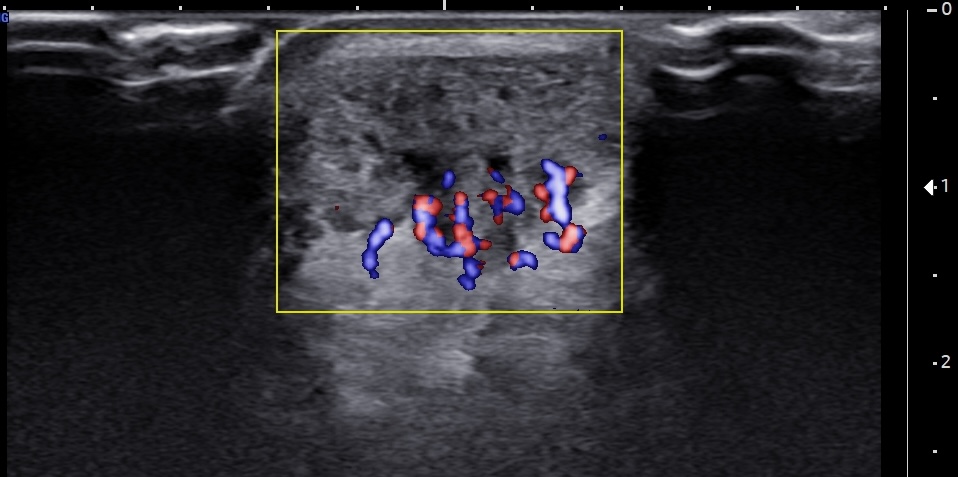

Short-axis ultrasound image of the pre-insertional Achilles tendon, a few millimeters proximal to the superior edge of the calcaneus, using color Doppler, demonstrating multiple neovessels within the retrocalcaneal bursa and the deep fibers of the tendon. Notably, the Doppler signal appears more prominent in the short-axis view compared to the long-axis images.